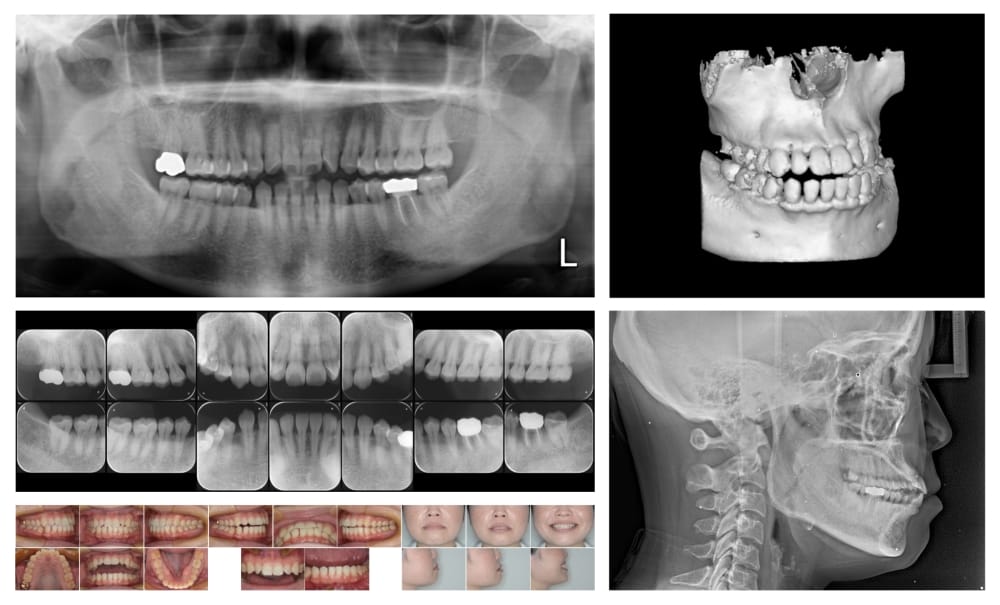

①精密検査でリスクを把握

奥歯のセラミックに痛みが出たり壊れたりする背景には、その歯の固有の問題と骨格や噛み合わせを含めた口全体の問題があります。安易で無計画なセラミック治療はトラブルの原因になります。例え1本の治療であっても事前に検査で問題点を抽出し、リスクに応じた治療計画を立てることが重要です。下高井戸デンタルオフィスでは治療前に必ず検査を行い、分析して治療方針を決めます。治療すべき歯の本数が多い場合やリスクが特に高いと思われる場合には、ここまで多くの資料を集めて慎重に検討する場合もあります。